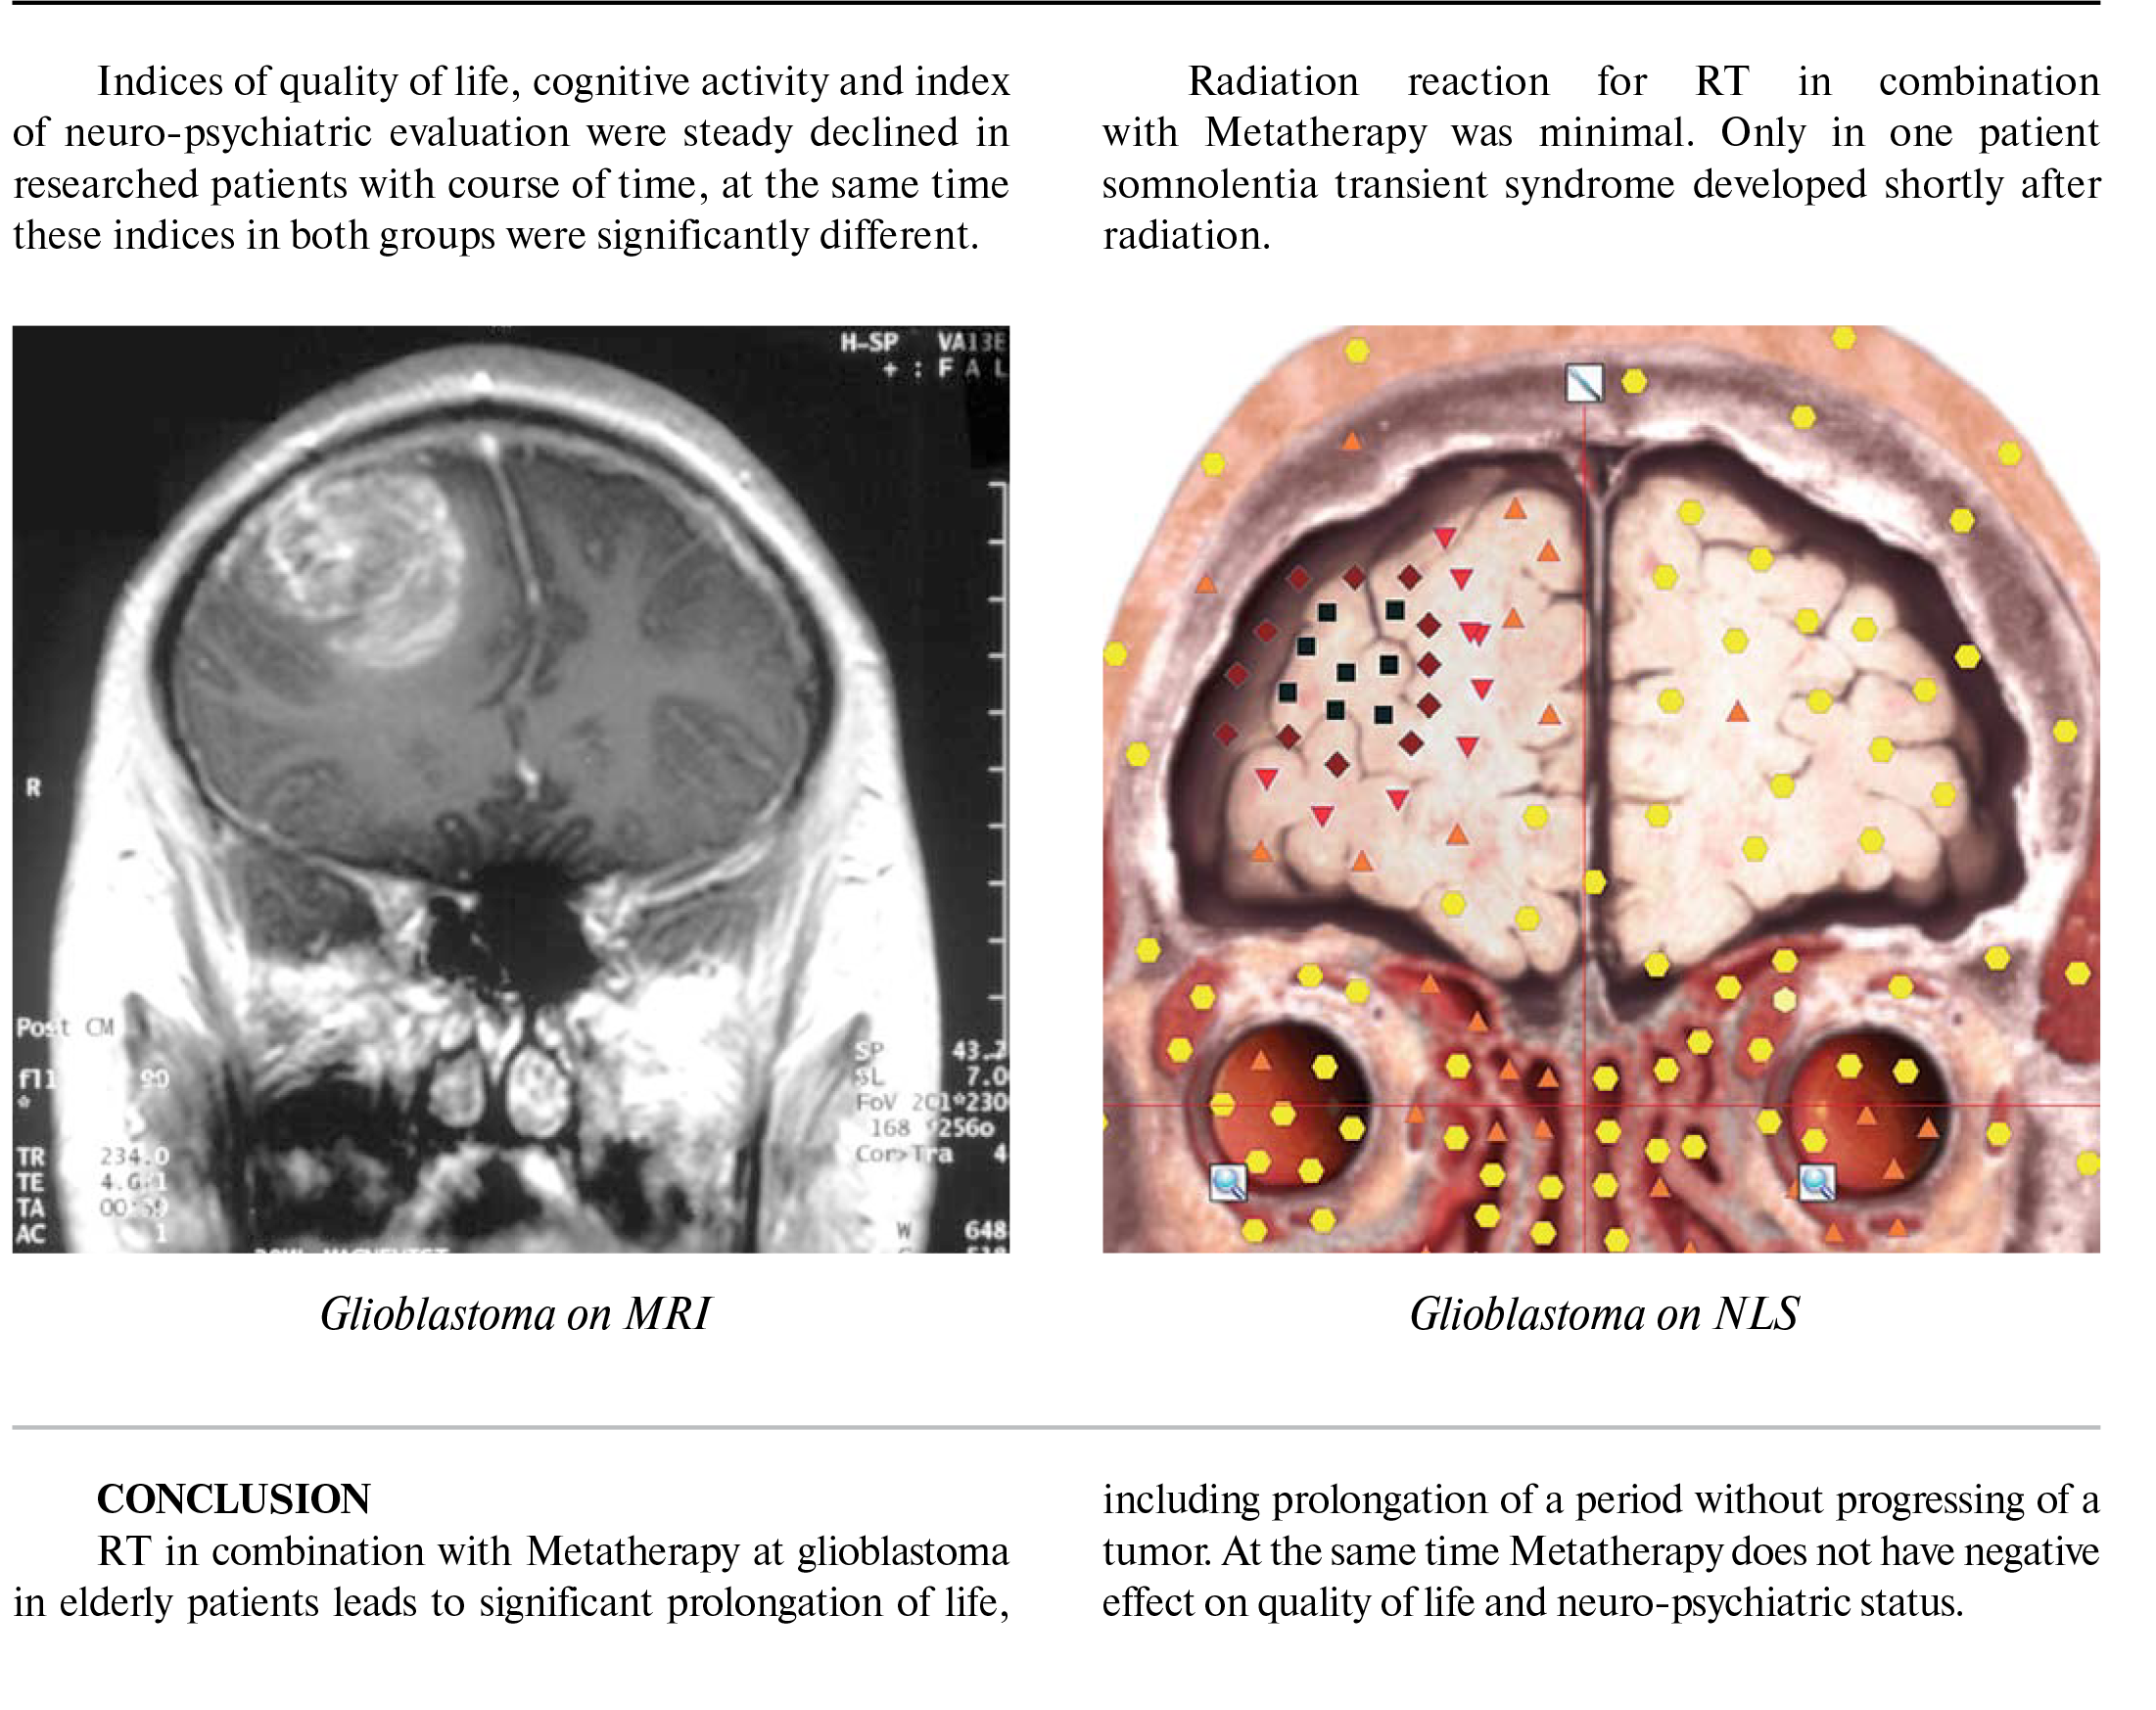

From www.bioresonancenls.com

Combined radiation therapy and metatherapy of glioblastoma in elderly How Effective Is Radiation For Glioblastoma the guideline panel endorses fractionated radiotherapy with concurrent and adjuvant temozolomide as the standard of care after biopsy or resection of. studies have shown that this combination is more effective than radiation without temozolomide. Whether and how radiation therapy should be applied. external beam radiotherapy (rt) has long played a crucial role in the treatment of glioblastoma.. How Effective Is Radiation For Glioblastoma.